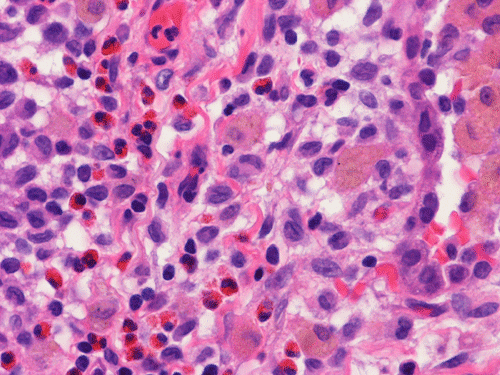

At scanning magnification (Panel A), the lung parenchyma is replaced by some coalescing fibrous nodules. The degree of involvement is variable at different fragments (Panel B and C). In the less affected areas, there are some fibrotic thickening of the septa (Panel C). In some areas, the changes are minimal and the pleural appear to be uninvolved (Panel D and E). In low to medium magnifications, these nodules of fibrosis contains a large number of hemosiderin laden macrophages (Panel F and G) admixed with fibrous tissue. The diagnostic tissue, however, is present in areas with increased cellularity. In these areas, there is a background of cells with a moderate amount of cytoplasm and bland nuclei. Some of these nuclei have kidney shape (arrow in Panel H). In some areas, many of the nuclei have a deep nuclear groove that resemble a coffee bean (arrow in Panel I). In the third type of areas, the nuclear grooving is not distinct (Panel J). Prominent eosinophilic infiltrations are almost always present. Immunohistochemistry on CD1a revealed many positive cells (Panel L). Also present in the specimen are multiple small blood vessels with thickened intima (Panel K). A Movat pentachrome stain demonstrates an internal elastic layer in these vessels and confirms that these are arteries (Panel M and N).

Histopathologic signature of Langerhans cell histiocytosis, namely kidney shaped or coffee bean shaped, bland nuclei associated with eosinophilic infiltration is not difficult to see in most of the cases. The amount of eosinophilic infiltration and the proportion of cells with nuclear grooving, however, can be quite variable but this problem can usually be overcome by a diligent search. Demonstration of CD1a by immuhonistochemistry or Birbeck granules by electron microscopy will confirm the diagnosis.

Pathologically, PLCH can be broadly divided into an early or cellular stage and a late or fibrotic stage. Demonstration of LCs is of critical importance for a correct diagnosis. The morphology of LCs is similar to LCH in other organs. LCs are characterized by a deep nuclear groove which lead to “coffee bean-shaped” or “kidney-shaped” nuclei. In most cases, the level of atypia and pleomorphism is low. A moderate amount of amphophilic to weakly eosinophilic cytoplasm is present. The cytoplasmic membrane is indistinct. Eosinophils and chronic inflammatory cells, varying from scant to abundant, are present. Except for a scant frankly pleomorphic cases, the level of pleomorphism and atypia is minimal to low. Eosinophilic abscesses with central necrosis may be present. Immunohistochemically, LCs are similar to their normal counter parts and are positive for CD1a and S100. At the ultrastructural level, Birbeck granules can be demonstrated. For most cases, the diagnosis can be established by histopathologic criteria but these additional features help to confirm the diagnosis.